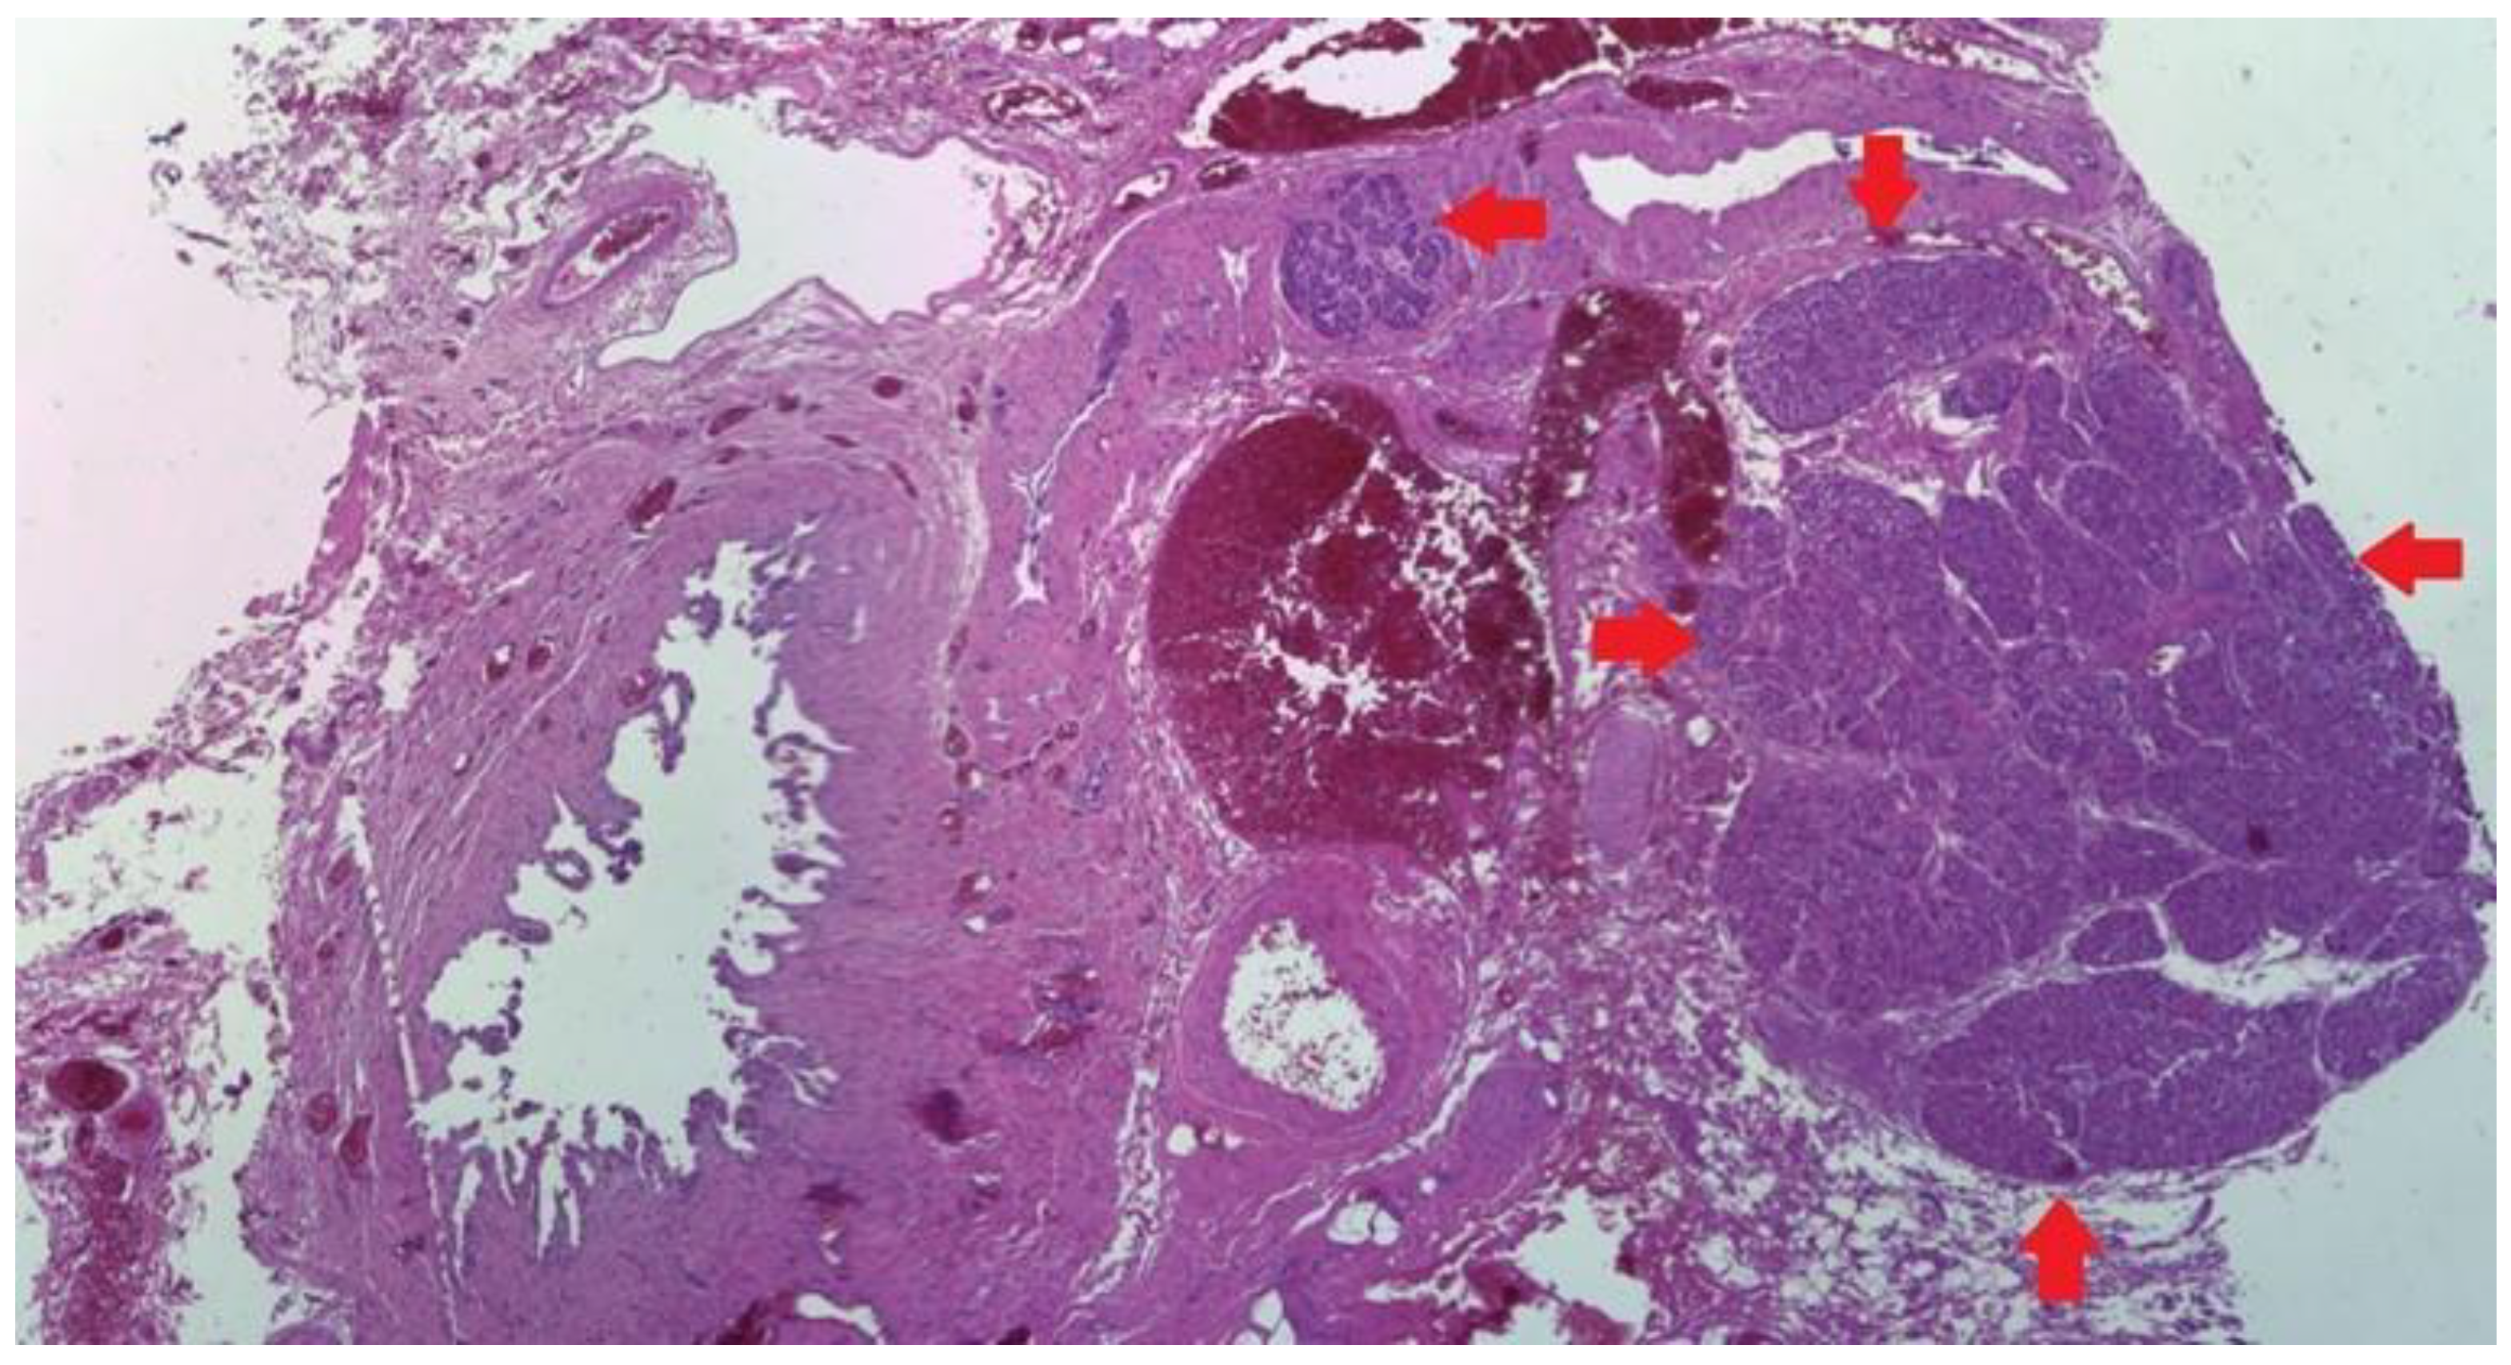

2.1. Type 1

2.2. Type 2

2.3. Type 3

3. Discussion